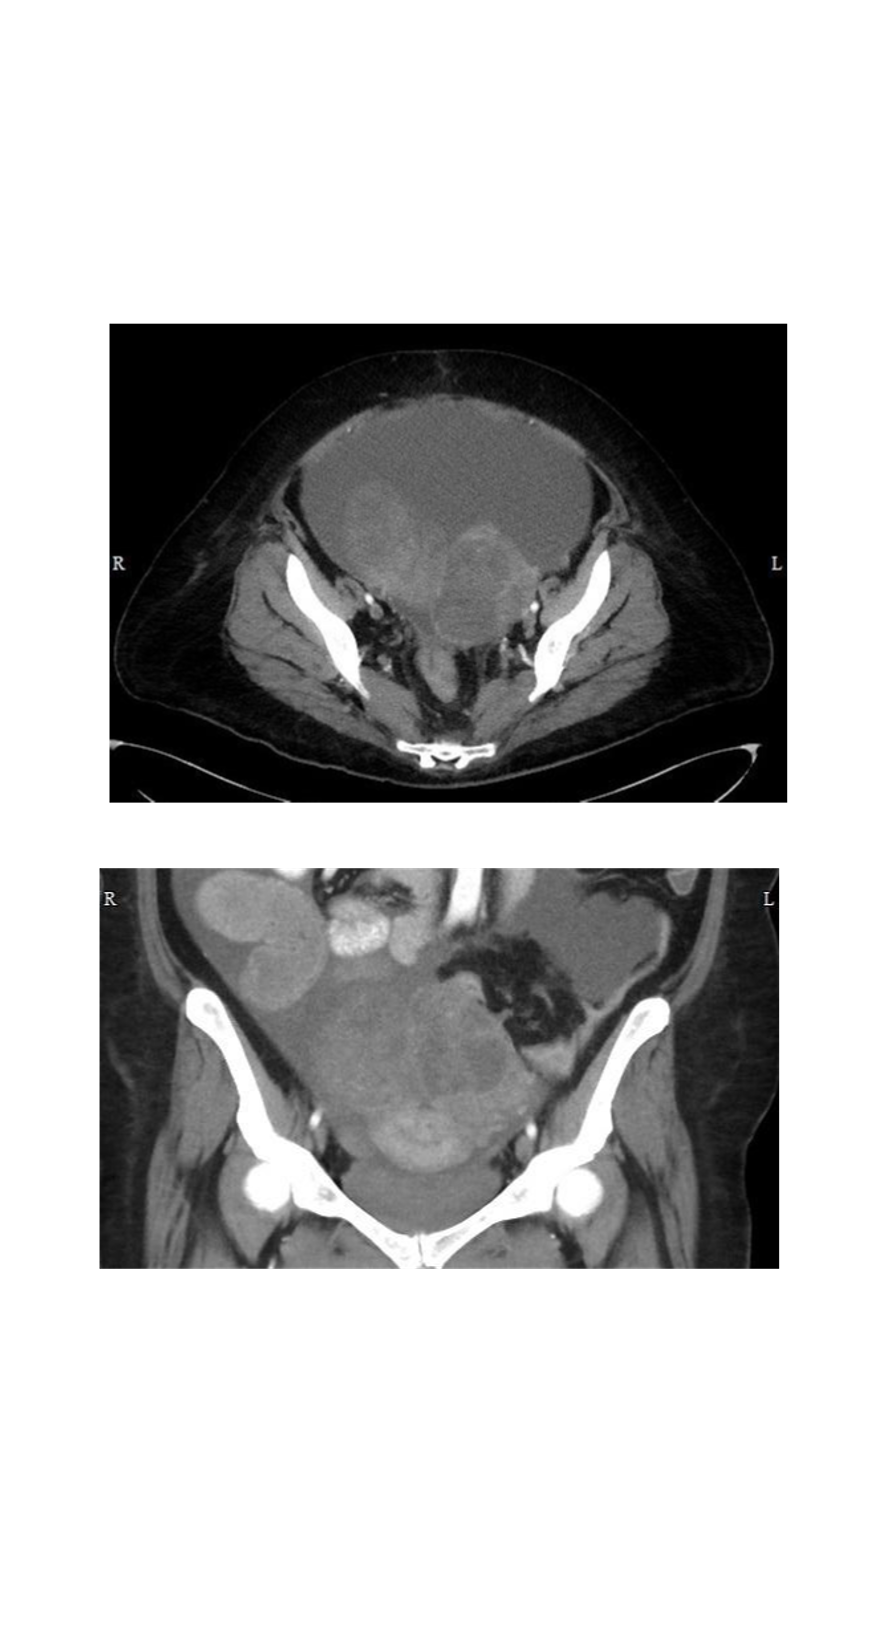

most likely metastasis to the ovary?

gastric cancer (most common!)

shown in the CT images are “Krukenberg” tumors - characterized by mucin sectreting “signet ring” cells

other cancers that met to ovaries are breast, lung, and contralateral ovarian cancer